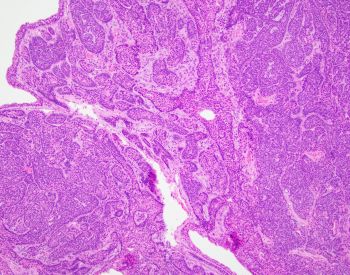

A 45-year old man with a history of PTC, tall cell variant (PT3b N1a M0), s/p total thyroidectomy, central neck lymph node excision and radioactive iodine therapy, presents with new neck mass. Figures a & b show FNA of the mass.